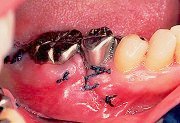

6

| 歯肉弁を縫合する前に、頬側に減張切開を加え、メンブレンをテンションが加わることなく覆えることを確認し、メンブレンに近い歯肉より縫合をすすめていく。 |